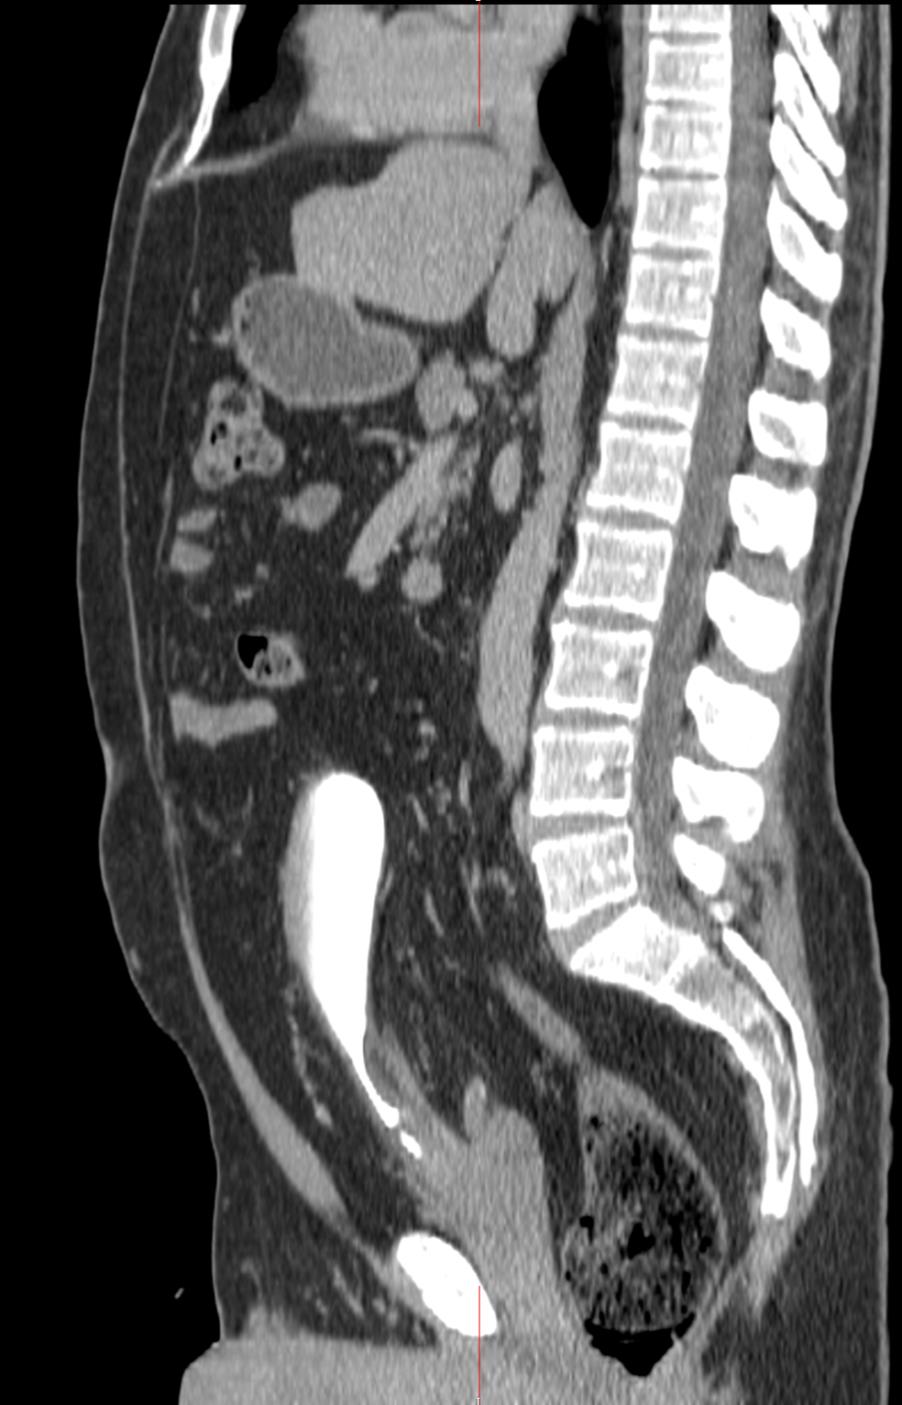

Fig 5. A sagittal CT image demonstrating a contrast-filled urinary bladder. |